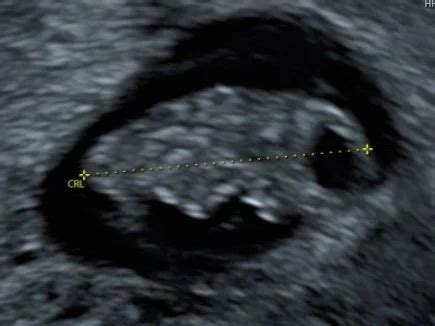

Een vroege echo, met name in het eerste trimester, biedt een zeer nauwkeurige manier om de uitgerekende datum te bepalen. Tijdens deze echo wordt vaak de CRL (Crown-Rump Length), de lengte van de baby van kruin tot stuit, gemeten. Als de meting van de echo afwijkt van de berekening op basis van de laatste menstruatie, volgt de zorgverlener doorgaans de datum die uit de echo naar voren komt.

Naarmate de zwangerschap vordert, worden echo's minder exact voor het bepalen van de datum, omdat baby's dan meer in grootte verschillen. Een vroege echo is daarom de meest betrouwbare methode voor het bijstellen van de uitgerekende datum.